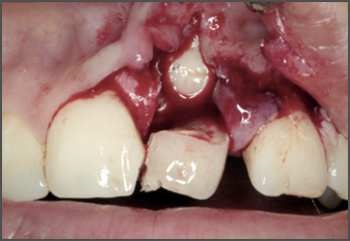

A cleft lip can range from a little notch in the coloured part of the lip to a complete separation of the upper lip which can extend up and into the nose. This can affect one side of the mouth (unilateral) or both sides (bilateral), and can be complete (meaning the cleft goes up into the nose) or incomplete.

A cleft lip can also affect the gum where the teeth come through. Again, this can range from a small notch to a complete separation of the gum into two parts.

Surgery is needed to close the gap left by the cleft. This will usually happen when the child is under a year old.

Every cleft is unique, just like every child, so the exact treatment pathway will vary. It may include further surgery to help with issues such as speech and growth of adult teeth. It may also include speech therapy, help with hearing, orthodontic work, etc.